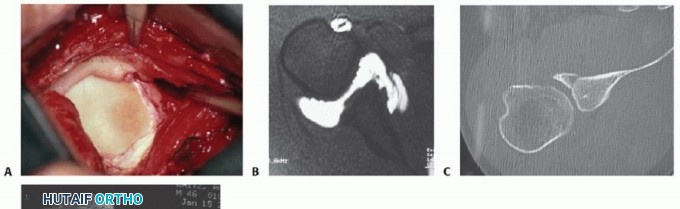

The “essential anatomic defect,” or Bankart lesion, first described by British pathologist A. Blundell Bankart in 1923, describes an avulsion of the anterior labrum and anterior band of the IGHL from the anteroinferior glenoid, typically as a result of a traumatic anterior shoulder dislocation (FIG 2A).

FIG 2 • A. The Bankart lesion: tear of the anterior inferior glenoid labrum. B. Axial view MRI scan showing the ALPSA. C,D. CT scan with axial view and reconstruction image, respectively, showing a large anterior inferior glenoid bony Bankart fracture.

The labrum may also be avulsed from the glenoid rim as part of a sleeve of tissue that includes glenoid

periosteum (anterior labral periosteal sleeve avulsion [ALPSA]) (FIG 2B).23 In these cases, the tissue displaces medially and may heal to the medial glenoid neck, with subsequent instability if left uncorrected.

Osseous fracture of the anterior inferior glenoid rim (“bony

Bankart” lesion) or more subtle attritional changes or glenoid wear may contribute to instability as well (FIG 2C).

In one study, three-dimensional (3-D) computed tomography (CT) identified bony changes in 90% of patients with recurrent anterior instability.27,33

Anterior or inferior bone loss of greater than 25%, resulting in a glenoid with an “inverted pear” appearance is associated with significantly increased risk of instability, often requiring reconstitution of the bony arc via either

primary repair or bony augmentation27 (FIG 2D*).